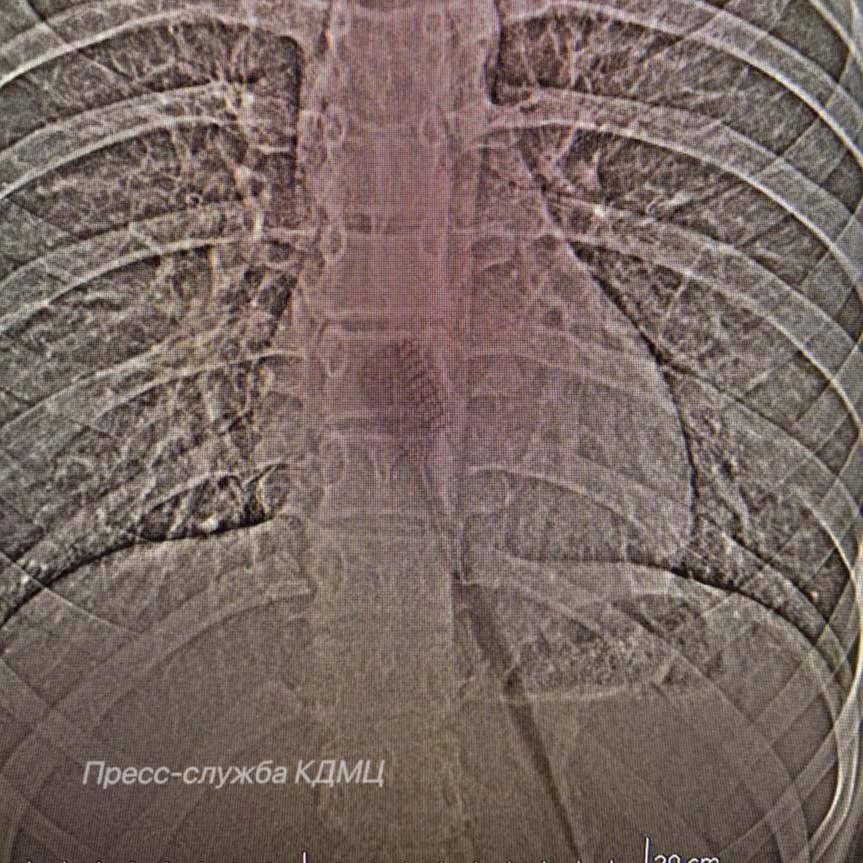

В КДМЦ из желудка тринадцатилетней девочки достали интересный предмет. Говорит, что 19-сантиметровую щётку проглотила, когда чистила зубы. Врачи считают, что ситуёвина могла случиться из-за глубокого вдоха или смеха.